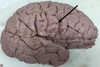

1. Identify the highlighted structure. 2. What is the primary function of this structure? 3. Identify this structure with regard to Brodman's Area.

Precentral Gyrus Primary motor area Area 4

71

1. Identify the highlighted structure 2. What is the primary function of this structure 3. Identify this structure with regard to broadmans area

1. Postcentral gyrus 2. Somatosensory area 3. 3,1,2